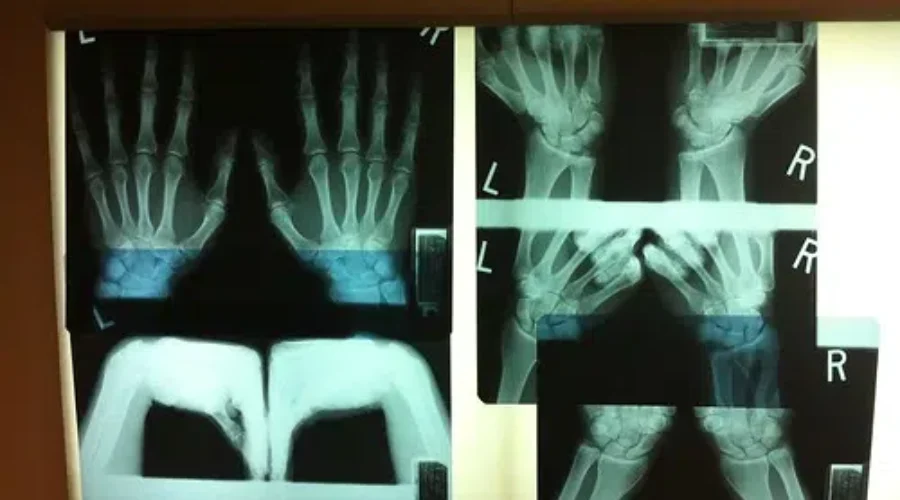

The Roseway Hospital Charitable Foundation has been fundraising to replace the current 22 year old analog X-ray machine with a new digital machine.

The updated machine will provide sharper images, and reduces the already low radiation rate even more.